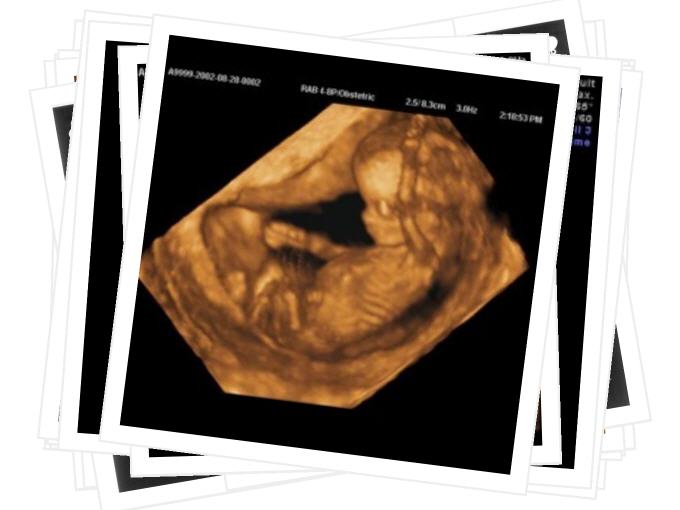

Geburtshilfe

Auf den folgenden Seiten können Sie sich einen Überblick über unser umfassendes Leistungsspektrum im Bereich Geburtshilfen und Pränataldiagnostik verschaffen.